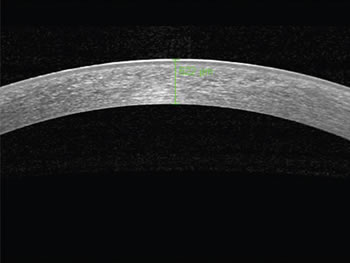

O OCT Spectralis de segmento anterior é útil para avaliação da córnea e suas patologias, bem como pós-cirurgia refrativa e adapatção de lentes contato. Pode se realizar medidas como a da profundidade do flap, do tamanho do filme lacrimal e da espessura da córnea em qualquer ponto escolhido.

A presença do modo ART que faz a média de 100 imagens fazendo com que a nitídez em detelhes do OCT SPECTRALIS de segmento anterior seja definitivamente a melhor que os OCTs de segmento anterior time domain.